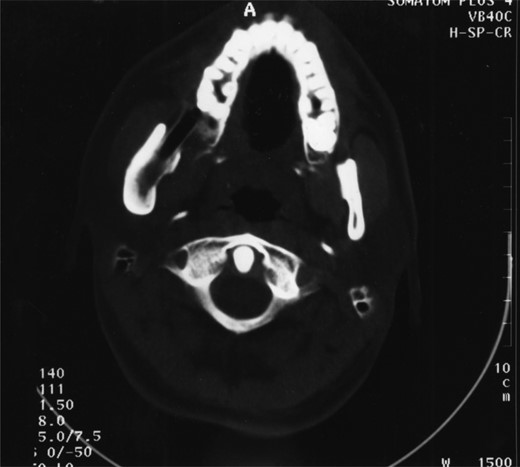

A 25-year-old man presented with a 2-month history of facial pain and limited mouth opening associated with a 3-week history of swelling of the right cheek. Radiographic analysis revealed a loculated, fluid-filled, well-demarcated lesion destroying and expanding the ascending ramus, extending out into the soft tissues, from the condyle down to the angle (Fig. 1).

A well-demarcated lesion extending out into the soft tissues from the ramus of the mandible.